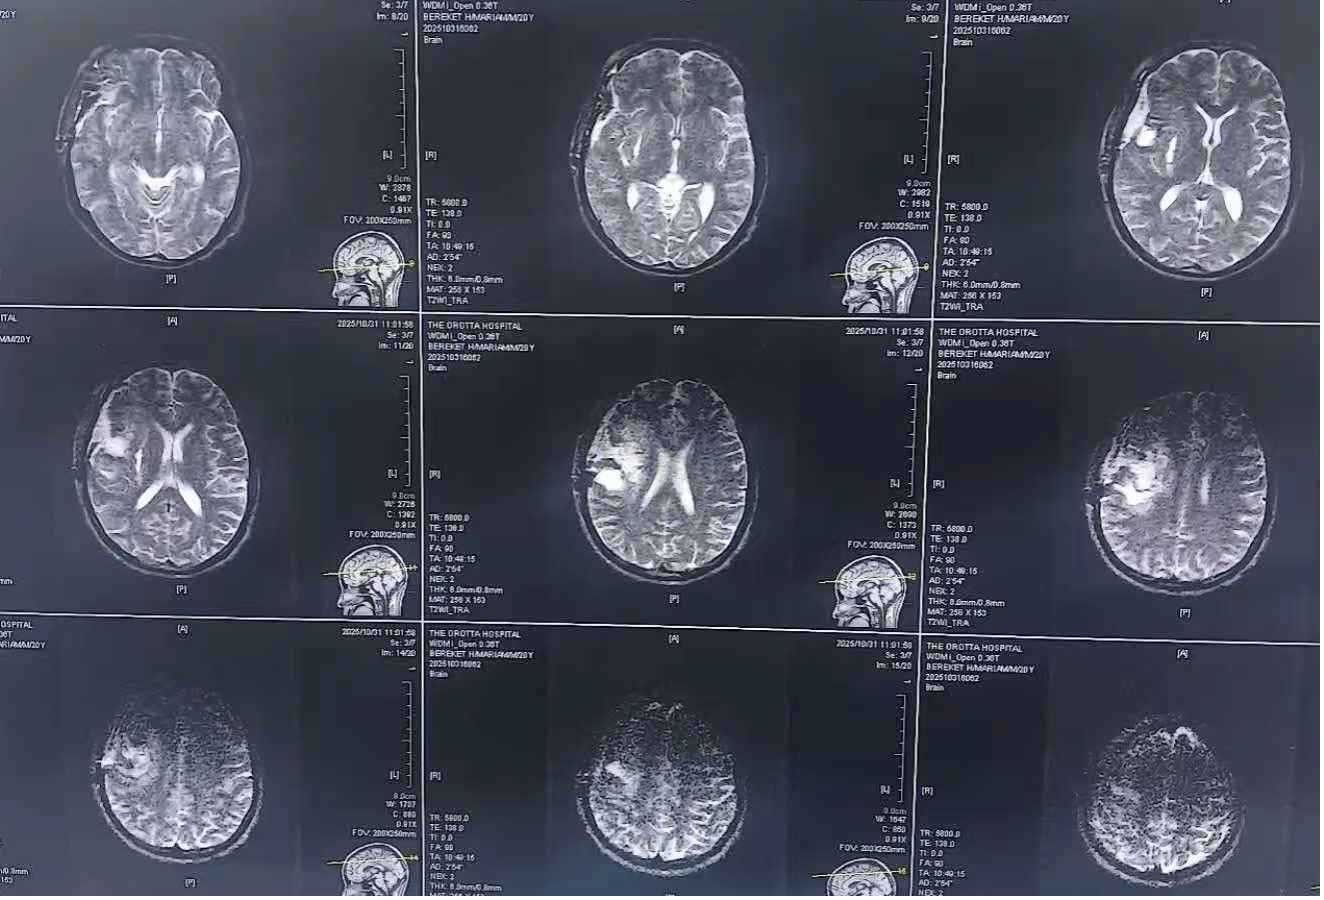

凭借多年临床积累的经验,李建东和张世军迅速制定周密手术方案。术前,两人反复研究患者CT影像,精准定位血管瘤位置与周围神经、血管的解剖关系;考虑到当地手术器械有限,李建东还利用从市第一人民医院带去的医疗耗材,提前做好应急准备。“援外前就预判到当地手术设备可能不足,特意携带了部分关键器械,没想到这次真的派上了大用场。”李建东说。

术后,在两位中国医生的精心诊疗和护理下,患者恢复情况远超预期。不仅成功脱离生命危险,意识逐渐清醒,仅遗留左上肢轻微活动障碍,后续通过康复治疗有望完全恢复正常。当患者家属看到术后MRI检查显示血肿清除干净、瘤体完整切除时,激动地向李建东和张世军竖起大拇指,用生硬的中文反复说着“谢谢”。